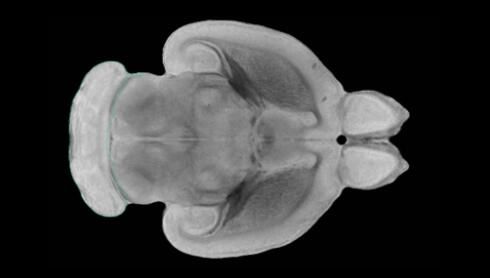

隨著(zhù)機體年齡增加,肌肉和關(guān)節都會(huì )變得僵硬,這就會(huì )使得日?;顒?dòng)變得更加困難,本文研究表明,我們的大腦也是如此,與年齡相關(guān)的大腦僵硬對大腦干細胞的功能或許有著(zhù)重要影響。文章中,研究人員對年輕和老化大鼠的大腦進(jìn)行研究闡明了年齡相關(guān)大腦僵硬對少突膠質(zhì)前體細胞(OPCs,oligodendrocyte progenitor cells)功能的影響。OPCs是一類(lèi)對維持正常大腦功能非常重要的大腦干細胞,其對于髓磷脂的再生也非常重要,髓磷脂是神經(jīng)組織周?chē)闹厩?,在多發(fā)性硬化癥中髓磷脂的再生常常會(huì )被損傷,機體老化對這些細胞的影響常常會(huì )誘發(fā)多發(fā)性硬化癥的發(fā)生,這些細胞的功能在老化的健康人群中同樣會(huì )下降。

為了確定老化OPCs的功能缺失是否可以被逆轉,研究人員將來(lái)自老化大鼠機體的老化OPCs轉移到了年輕大鼠柔軟的海綿狀大腦組織中去,值得注意的是,這些老化的大腦細胞能夠重新恢復活力,其行為非常像年輕更加強壯的細胞。這項研究中,研究人員在實(shí)驗室中開(kāi)發(fā)出了具有可變僵硬程度的新型材料,并在受控環(huán)境下研究這些材料的生長(cháng)及其對大鼠大腦干細胞的影響,這些材料能被工程化改造具有和年齡或老化大腦相似的柔軟程度。

為了深入理解大腦組織柔軟和僵硬影響細胞行為的分子機制,研究人員對細胞表面一種名為Piezo1的蛋白質(zhì)進(jìn)行了分析,該蛋白質(zhì)能“告知”細胞其周?chē)沫h(huán)境為柔軟或僵硬。研究者Kevin Chalut說(shuō)道,我們發(fā)現,當在僵硬材料上促進(jìn)年輕具有功能性的大鼠干細胞時(shí),這些細胞就會(huì )表現出功能異常,并失去其再生的能力,實(shí)際上其行為與老化細胞相似。當將老化的大腦細胞在柔軟材料上生長(cháng)時(shí),其功能就會(huì )表現得像年輕細胞一樣,換句話(huà)說(shuō),其能夠重新恢復年輕的活力。

當研究者從老化大腦干細胞的表面剔除Piezo1蛋白后,他們就能夠誘騙細胞感知柔軟的周?chē)h(huán)境,甚至當將細胞在僵硬材料上生長(cháng)時(shí)也是如此。此外,當在老化大鼠大腦中剔除OPCs上的Piezo1時(shí),就會(huì )促進(jìn)細胞變得年輕并再次承擔正常的再生功能。研究者Susan Kohlhaas表示,多發(fā)性硬化癥是一種痛苦讓患者致殘的疾病,隨著(zhù)時(shí)間推移,我們迫切需要開(kāi)發(fā)出減緩并抑制患者殘疾的新型療法。這項研究中,研究人員闡明了大腦干細胞老化的分子機制,以及如何通過(guò)逆轉該過(guò)程來(lái)實(shí)現恢復大腦干細胞活力,后期研究人員將會(huì )基于本文研究開(kāi)發(fā)出新型療法來(lái)治療多種與老化和多發(fā)性硬化癥相關(guān)的疾病,包括如何潛在恢復大腦失去的功能等。